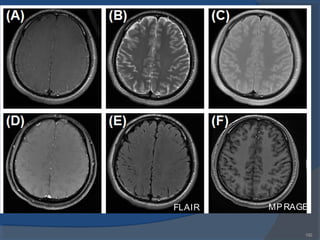

MPRAGEFLAIR

151151

FLAIR (FLuid Attenuated IR)

 Inversion recovery sequence with long TI

 The TI is set to the zero crossing point of fluid→

suppression of signal from csf

 Lesions that are normally covered by bright fluid

signals using conventional T2 contrast are made

visible by FLAIR

FLAIR (Fluid Attenuated Inversion Recovery) Sequence

Thesameprincipleasused for signal suppression of fat

tissuein STIR can also beused to suppresssignal from

CSF. With aTI of around 2000 msthesignal from CSF is

effectively suppressed. An Inversion Timeof 2000 ms. in

combination of along TE isused to study demyelinating

diseases, such asMultipleSclerosis. With thisTI value,

MultipleSclerosislightsup likealight bulb, because

normal fluid issuppressed. FLAIR issubstantially more

sensitivefor demyelinating diseasesthan ordinary T2